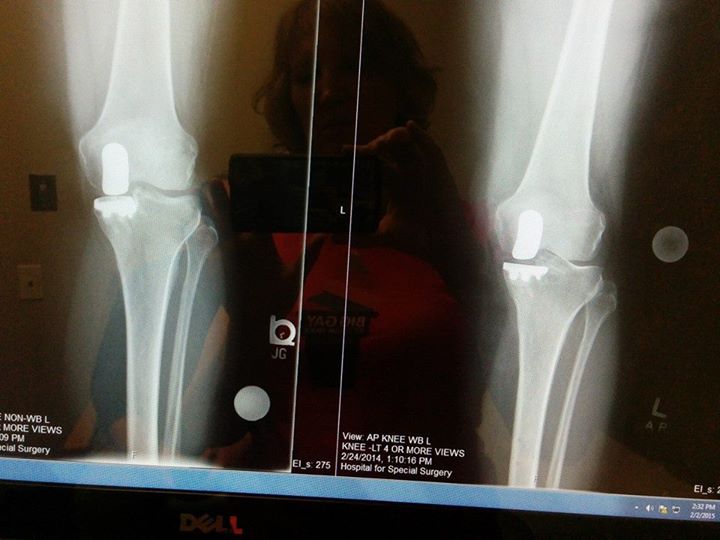

I used to hike on weekends and walk to work every day, and in 2007 I had a meniscus tear that was treated with arthroscopy. I had no pain again until late 2011: trotting across the street to make a light, suddenly I felt my knee grind painfully. I thought, no problem, but it turned out to be a big problem. The pain got worse and worse. By July, I was unable to walk more than a few feet. I went from one knee specialist to the next from 2012 to 2014. They tried repeat courses of hyaluronic acid injections to the knee joint, and cortisone shots along with physical therapy, but nothing worked for very long. I had a pronounced limp and it threw my alignment off so much that several discs in my back began herniating.

By the time I came to HSS I was almost unable to walk. I had to use an offloading brace to keep the bones of my knee from grinding into each other. Physical therapy was limited by the pain in my back. The herniated discs and arthritis in my spine meant I had to work from bed because it was too painful to travel to work or sit in a chair.

Dr. Pearle performed a partial knee replacement in February of 2014. It took a couple of months to recover, but by May I was able to walk around in the French Alps with my husband. By summer I was climbing my favorite trail, Breakneck Ridge, a couple of times a month. Right after my 1 year anniversary, we climbed around Machu Picchu and the Sacred Valley of Peru together. Dr Kramskiy is helping me address my spine pain, and I'm still doing physical therapy to build back my strength and help keep my spine functional, but the pain is gone, and I've got my life back.